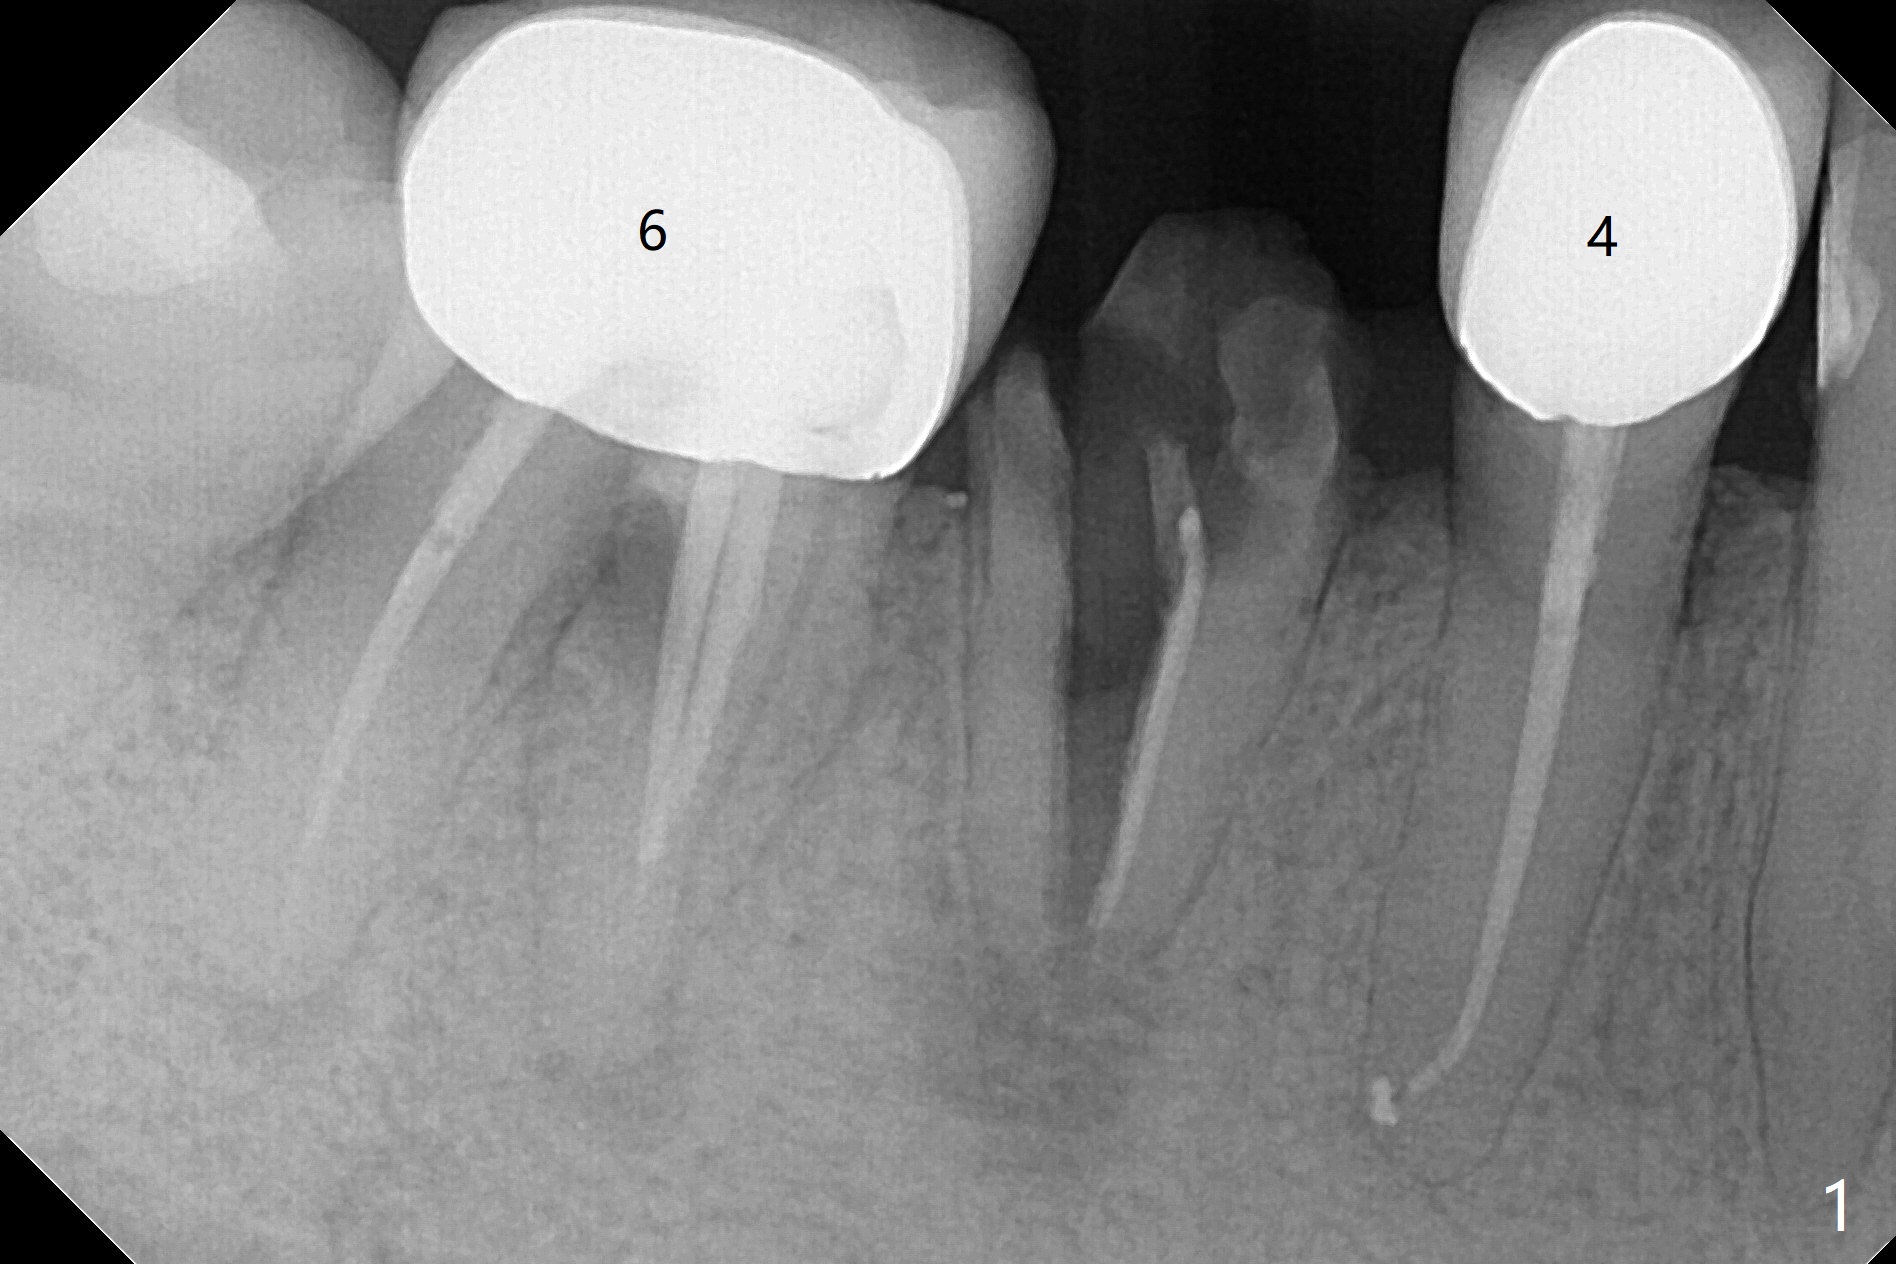

今天遇见一位特殊病人,54岁女,“右下一个牙齿断裂,我觉得一定要拔 (图一:5)。能不能同时种牙,减少痛苦。不过你是医生,一切由你决定”。为了炫耀,介绍导板,她还没有提钱的问题,估计必须再等十年才能碰见怎么有远见的土豪(夸张)。所以我们迫不及待拍摄CT,然后取模。至今有没有不对的地方,尤其是拍摄CT。要做导板周围(前后)有牙冠,在拍摄CT下,会产生折射(图二:*),影响CT精确度,不能与口内模型互相融合,从而影响导板精确度。如果实在想做导板,必须事先在牙冠上制作树脂cone(图三:红色三角形),然后拍摄CT和取模(或者scan),实验员才能准确融合两个图像。对于这个病例,只能做徒手种植,减少射线。不过增加手术时间,为了不损伤颏神经(图四),可能需要多次拍摄根尖片,增加无限的烦恼,一失足成千古恨。但是不会失去最后一个手段:PRF。